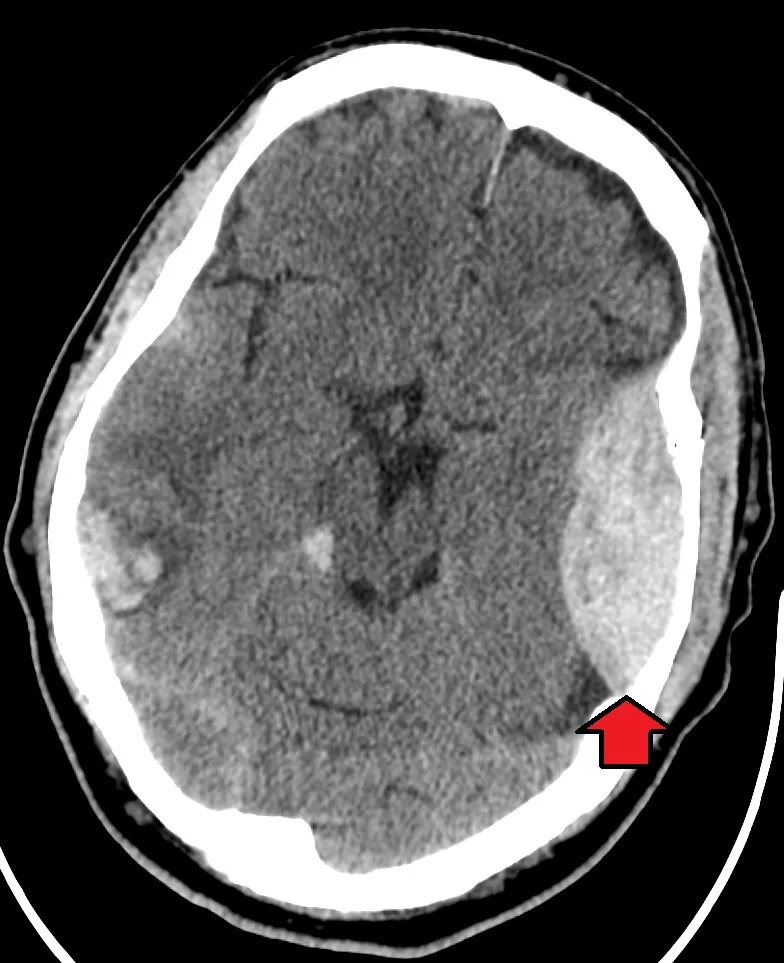

Subdural Hematoma (SDH)

- Shape: Crescent-shaped, concave, layering along the cerebrum.

- Boundaries: Crosses suture lines but is limited by dural reflections (falx, tentorium).

- Density: Varies with age:

- Acute (<3 days): Hyperdense

- Subacute (3d-3w): Isodense

- Chronic (>3w): Hypodense

- 📌 Mnemonic: Subdural = Banana.

⭐ Midline shift >5 mm on CT is a critical finding. A "swirl sign" (mixed density) within an acute hematoma suggests active bleeding and predicts expansion.